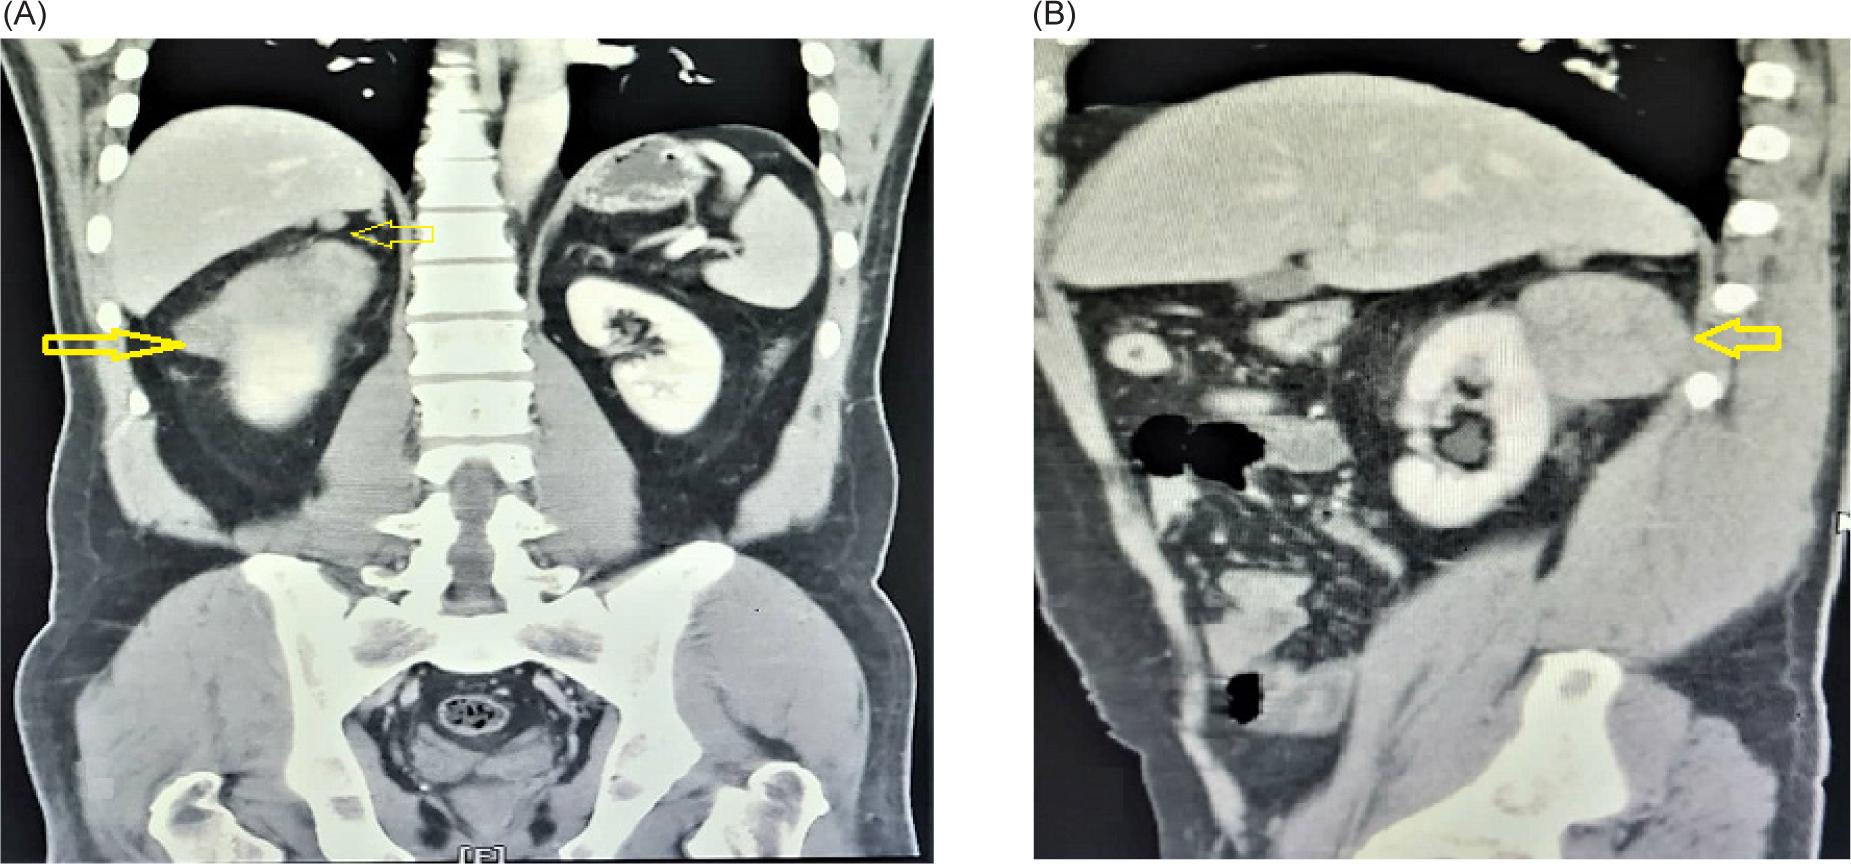

The ultrasonography (US) of the abdomen revealed an ill-defined and exophytic right renal mass, which measured 62 × 87 mm, arising from the upper pole of the right kidney. The abdominopelvic computed tomography (CT) scan revealed lobulated soft tissue mass in the posterior pararenal space, compressing the right kidney. The mass had mild contrast enhancement and cystic change without calcification and measured about 71 × 45 × 54 mm. There were two hypodense nodule masses measuring about 12 × 8 mm and 6 × 4 mm in the right posterosuperior aspect of pararenal space, which invades the liver organ. Another hypodense nodule mass measured about 20 × 15 mm located lateral to inferior vena cava (IVC). There was some fat stranding around the masses but no signs of organ invasion (Figure 1). Previous sonography-guided true-cut biopsy from the kidney mass showed spindle-cell tumor with smooth muscle differentiation, suggestive of low-grade sarcoma.

FIGURE 1: A computerized tomography (CT) scan showed: (A) Mass in the right kidney (arrow), two masses were attached to the liver tightly (arrow). (B) Oblique view of mass in the right kidney with low enhancement (arrow).

IMT laboratory findings were varied, with no evident abnormality in laboratory tests (1). The reported US findings of renal IMT are hypoechoic or hyperechoic change with internal vascularity. However, it may not be conclusive (7). Abdominal CT scan and magnetic resonance imaging (MRI) are helpful radiologic diagnostic methods. However, they may be associated with nonspecific findings and various clinical presentations (7). The lesions may arise from the renal cortex or the pelvis, with well-defined or ill-defined margins with varied density ranges, enhancement degrees, and patterns. In addition, cystic change and calcifications may present (11). In our case, CT revealed a mass in the posterior pararenal space arising from renal cortex; two masses invaded the liver organ and another mass was near the IVC. All masses had varied enhancement degrees, typically indicative of malignant lesions.